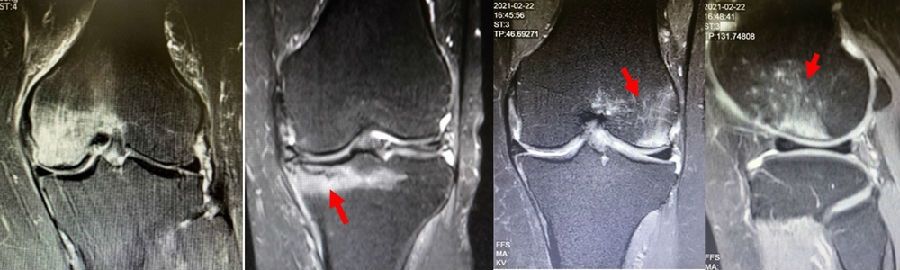

病例:女,65岁,主诉左膝关节内侧疼痛2月余。2017年11月X光未见左膝骨质异常。MR见股骨内侧髁骨坏死,半月板相对突出百分比(RPE)28.3%,合并内侧半月板后根部撕裂,矢状位病变区域前后径为11.67mm,关节线会聚角2.68°

2018年2月复查MR见骨髓水肿明显吸收,坏死灶边界清晰,半月板相对突出百分比(RPE)28.92%

2018年6月复查MR见骨髓水肿基本完全吸收,坏死区修复良好,半月板相对突出百分比(RPE)38.54%,患者临床症状消失。

提示坏死好转了,但半月板突出进展了,膝关节的退变加重了。